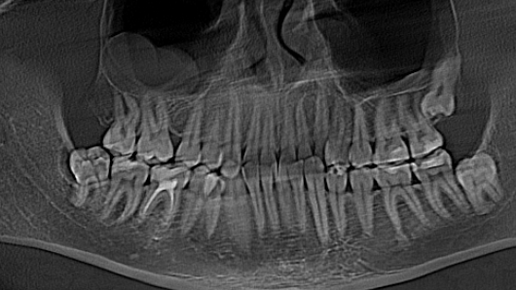

Разговоры о зубах мудрости вызывают много сомнений: одни жалуются на невыносимые боли, другие даже не замечают, что восьмерки прорезались, третьи — жалеют, что не удалили их, как можно раньше. В статье стоматолог «Белой радуги» Журов Илья Владимирович ответит на часто задаваемые вопросы о зубах мудрости и расскажет, что с ними все же следует делать. В статье поговорим о том: Что такое зубы мудрости и для чего они нам нужны У человека есть 4 типа зубов: резцы, клыки, премоляры и моляры. Зубы мудрости — это третьи моляры...

Зубы мудрости – проблема для современного человека и хороший заработок для стоматологов. Редко можно встретить того, кому зубы мудрости не доставляют беспокойства. Им обычно не хватает места в полости рта, поэтому зубы мудрости растут криво, впиваясь в десны. Удалять такие зубы всегда проблематично, их корни расположены рядом с нервными окончаниями. Осложнения после удаления зубов мудрости случаются часто. Зачем нам нужны зубы мудрости? Поговорим об этом в нашей статье. Нужны ли нам зубы мудрости? Так называемые «восьмерки» обычно вырастают до 25 лет...